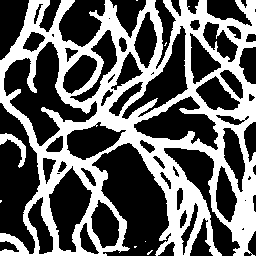

Semantic segmentation of blood vessels is an important task in medical image analysis, but its progress is often hindered by the scarcity of large annotated datasets and the poor generalization of models across different imaging modalities. A key aspect is the tendency of Convolutional Neural Networks (CNNs) to learn texture-based features, which limits their performance when applied to new domains with different visual characteristics. We hypothesize that leveraging geometric priors of vessel shapes, such as their tubular and branching nature, can lead to more robust and data-efficient models. To investigate this, we introduce VessShape, a methodology for generating large-scale 2D synthetic datasets designed to instill a shape bias in segmentation models. VessShape images contain procedurally generated tubular geometries combined with a wide variety of foreground and background textures, encouraging models to learn shape cues rather than textures. We demonstrate that a model pre-trained on VessShape images achieves strong few-shot segmentation performance on two real-world datasets from different domains, requiring only four to ten samples for fine-tuning. Furthermore, the model exhibits notable zero-shot capabilities, effectively segmenting vessels in unseen domains without any target-specific training. Our results indicate that pre-training with a strong shape bias can be an effective strategy to overcome data scarcity and improve model generalization in blood vessel segmentation.